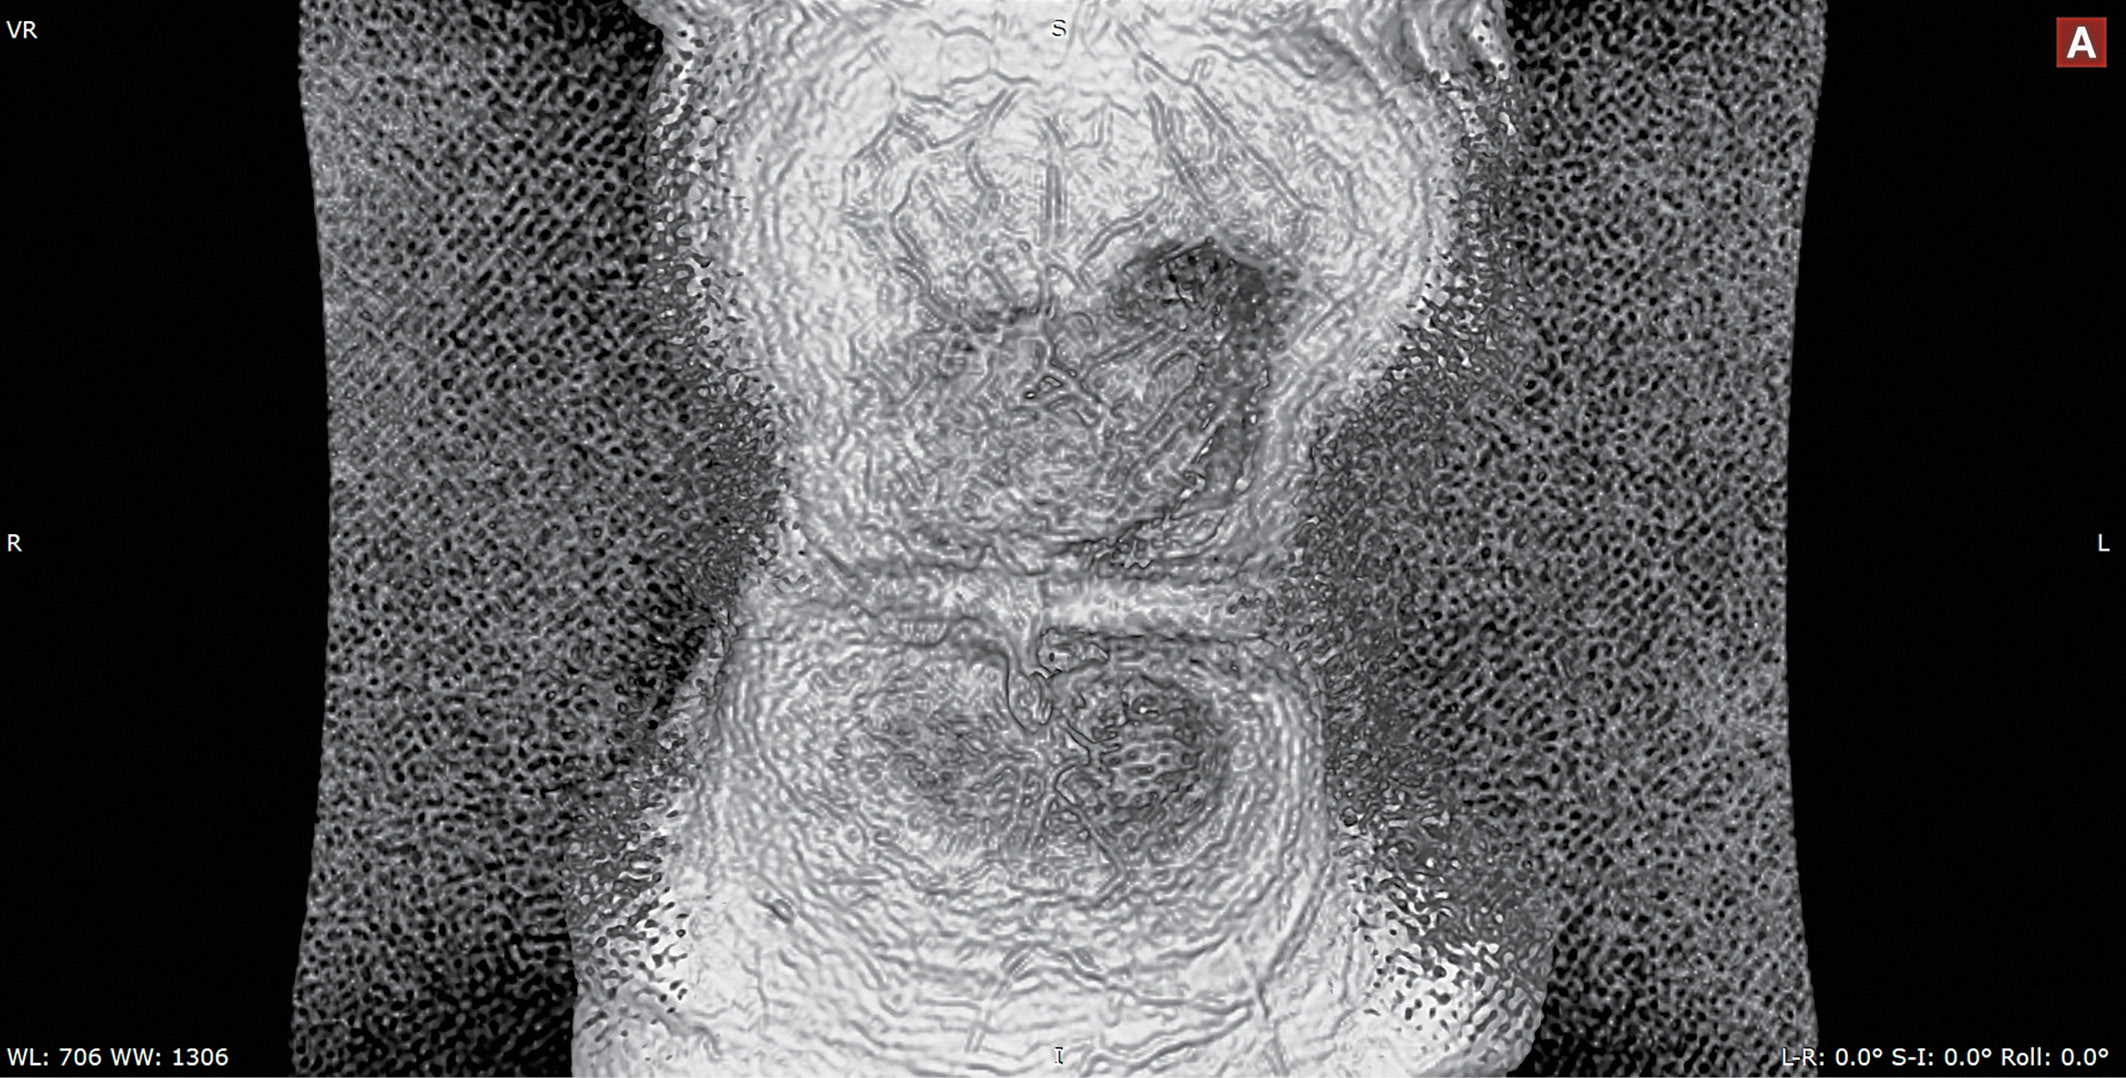

8. Fig. 8. 3D reconstruction of MRI images of the subcutaneous vessels of the anterior abdominal wall in a patient with diabetes mellitus: MR-tomograph General Electric Discovery MR750W (magnetic field 3.0 T). Coil: Body 48 AA, reconstructed diameter 400 mm, matrix 320x320. Technology: T2-WI FS Rtr Propeller (selective fat reduction; TR 4000.04 ms; TE 95.76 ms, 3 mm cut). The image was obtained in 3D-Volume Rendering mode (multi-planar surface reconstruction; Skin B / W was used in all cases) in the RadiAnt DICOM Viewer Ver program. 5.0.1.21910 (64-bit) [51]. In the zone of lipohypertrophy to the left of the umbilical ring (mirror image), the density of blood vessels is higher than in the contralateral zone, but the vascular tree is less structured (chaotic). | |

(472KB)